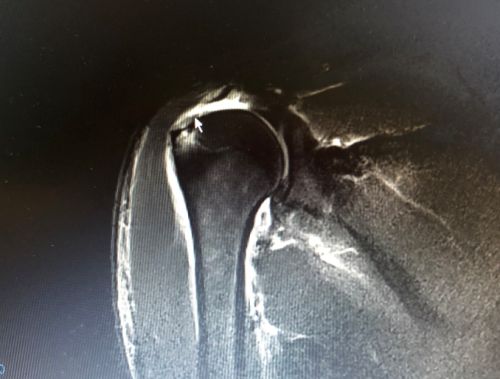

核磁共振显示,右侧冈上肌肌腱断裂回缩。

入院后完善相关检查,核磁共振证实了之前的判断,患者右侧冈上肌肌腱和肩胛下肌肌腱全层断裂并回缩,这种情况是不可能自己长好的,除了会出现肩部反复疼痛以外,肩部力量也会逐渐下降,只能手术修复。王靖主任为患者制定了手术方案,并于9月11日带领团队为患者施行全麻下右肩关节镜检查、肩袖缝合手术。